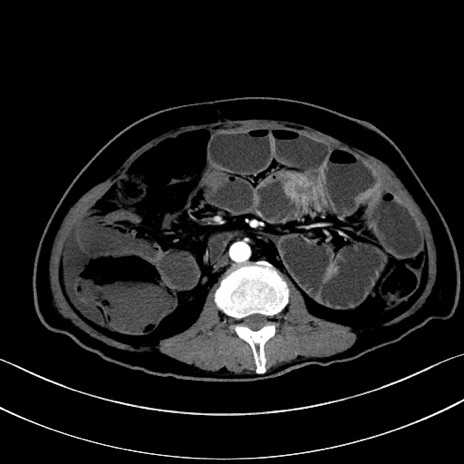

冠状断像

【症例】60歳代男性

【主訴】嘔吐

【現病歴】胃癌にて胃全摘後。食思不振が悪化し、夜中に嘔吐することがある。

【既往歴】胃癌、胃全摘、脾摘、胆摘後

【データ】WBC 5900、CRP 10.56